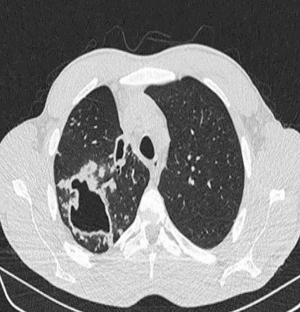

Traditionally thoracic surgery was concentrated on management of tuberculosis (8,9). The magnitude of impact of tuberculosis on mankind was huge and techniques for surgical removal of the diseased lung and obliteration of cavities in the chest were developed to tackle these problems. Role of the surgical team in tuberculosis is mainly for diagnostic purpose, excision of troublesome disease in drug resistant cases, symptomatic relief in haemoptysis, empyema or recurrent chest infections or to deal with one of its long-term sequelae. But, even going by the advances of modern day healthcare, thoracic surgery in case of complicated tuberculosis is quite challenging for the surgeon as well as the anaesthesiologist. Takeda et al. identified aspergillus coinfection, major preoperative comorbidity, long duration of surgery, need of blood transfusion and male gender as risk factors for adverse perioperative outcomes (10). Worldwide, VATS has shown promising results and thoracic surgeons are increasingly confident of the fact that tuberculosis is not a contraindication for VATS. VATS intervention is quite effective in reducing the mortality and morbidity of tubercular sequelae of lung (Figure 1). As a precautionary measure, the preoperative team should take a serious note of any haemoptysis as it can be life threatening at times as the dead space volume of 150–200 mL can be easily filled by blood compromising the airway (11). Establishing the site of the haemoptysis is also important to decide upon lung isolation and bronchoscopy. In areas where conventional lung isolation facilities are unavailable, anesthetist can advance a single lumen tube into the healthy side and continue with volume resuscitation process. The patient can then be shifted to a higher set up for definitive treatment like surgery or bronchial artery embolization.